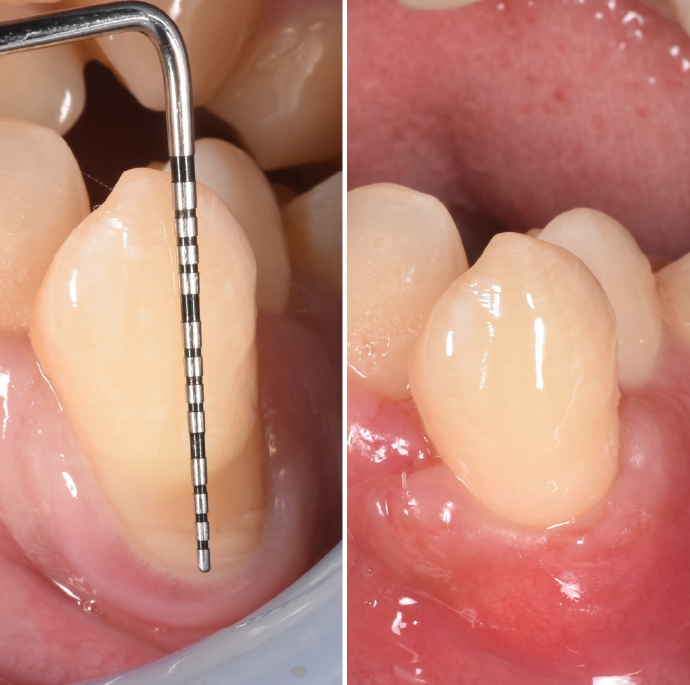

患者様お一人おひとりのお口の状態を、レントゲンやCT、歯周ポケットの深さなどを含む精密な検査で把握します。

歯茎の上の歯垢・歯石に対してはスケーリング、歯茎の下(歯周ポケット内)に入り込んだ歯垢・歯石に対してはルートプレーニングを行います。これにより歯の表面を滑らかにして、汚れが再付着しにくい環境を作ります。

SRPでも改善が見られない重度の症例では、歯肉を切開してポケット奥深くまで歯石などを除去する外科的処置を行います。

| 治療内容 | 全て 根面被服術(歯茎を上げる手術) |

| 治療費 | 総額 88000円〜 |

| 治療回数 | 1回 |

| リスク | 術部の発赤、腫脹、疼痛、部分的なネクローシス |